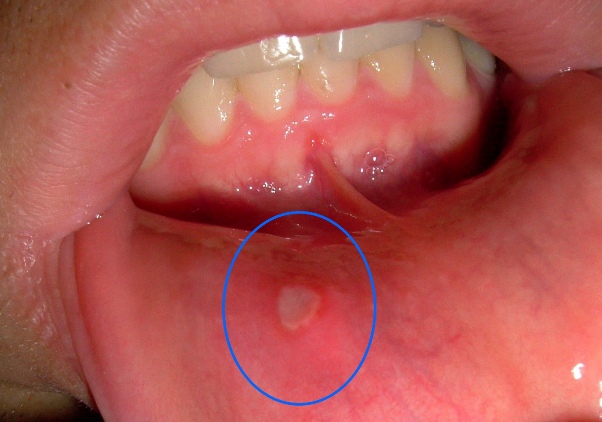

Afte su male, bolne ranice koje se javljaju unutar usne šupljine, na jeziku, usnama ili sluznici usne šupljine. Iako često nisu ozbiljan zdravstveni problem, ove ranice mogu izazvati veliku nelagodu, osobito prilikom jela, pijenja ili govora.

Ponekad mogu postati i veliki izazov za svakodnevne aktivnosti, jer mogu otežati uživanje u hrani ili čak razgovoru. U ovom članku ćemo se baviti prirodnim načinima liječenja afti i pružiti korisne savjete za ublažavanje simptoma.

Iako afte obično nisu ozbiljan zdravstveni problem i obično nestaju same od sebe u roku od 7 do 10 dana, postoje situacije kada bi trebalo potražiti medicinsku pomoć. Ako su afte izuzetno velike, bolne i ometaju vašu sposobnost normalnog jela i govora, ili ako se pojavljuju vrlo često, obavezno se konzultirajte s liječnikom. Također, ako su afte popraćene visokom temperaturom ili drugim simptomima infekcije, odmah se obratite stručnjaku.

U zaključku, afte, iako obično bezopasne, mogu izazvati veliku nelagodu. Kombiniranjem prirodnih tretmana, zdravih životnih navika i pravovremenog medicinskog savjeta, možete se riješiti tih bolnih ranica i poboljšati zdravlje svoje usne šupljine.